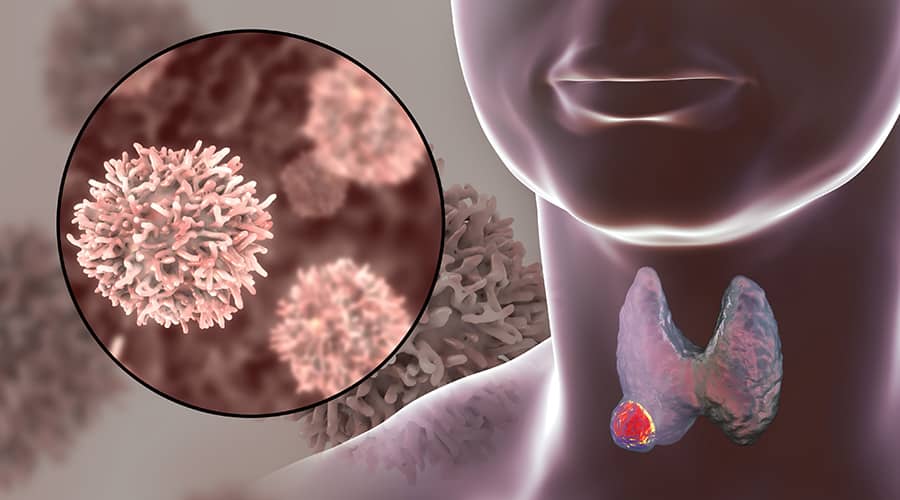

Benign or Malignant? Screening for Thyroid Cancer

Thyroid cancer statistics In 2022, the American Cancer Society reported about 43,800 new cases of thyroid cancer (11,860…